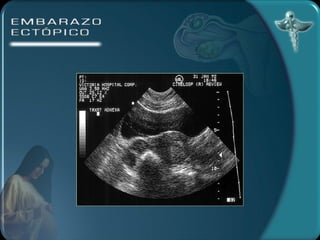

DIAGNÓSTICO Por imagen Ecografía transvaginal útero vacío 100% tumor parauterino 85 % embrión 55% Anillo tubárico Líquido en el fondo del saco

DIAGNÓSTICO Por imagenEcografía transvaginal útero vacío 100% tumor parauterino 85 % embrión 55% Anillo tubárico Líquido en el fondo del saco

• #23 DIAGNÓSTICO )LABORATORIO: la hemoglobina y el hematocrito pueden ser de utilidad para el seguimiento de la paciente. Estos valores pueden no alterarse precozmente ante una hemorragia.La leucocitosis puede estar presente en el 50% de los casos mientras que el otro 50% permanece con valores normales.La gonadotrofina coriónica humana puede investigarse en suero o en orina. Las pruebas urinarias son de poca sensibilidad en esta patología. Con la prueba de ß HCG en suero se puede detectar todo tipo de embarazos. Los niveles de la ßHCG se correlacionan con la edad gestacional. Durante las primeras 6 semanas de gestación los niveles séricos se incrementan en forma exponencial ( la duplicación del valor de la ßHCG es constante), después de las 6 semanas (nivel de la ßHCG de 6000 a 10000 mUI/ml) el ascenso se hace más lento y menos constante. Cundo los niveles de ßHCG son bajos (por debajo de 1000 mUI/ml) el valor absoluto es menos útil para diferenciar un embarazo normal de uno extrauterino. 2) ECOGRAFÍA TRANSABDOMINAL A) ÚTERO VACÍO B) MASA ANEXIAL C) LÍQUIDO EN EL FONDO DE SACO Con este método no es posible diagnosticar embarazos pequeños de 5 a 7 semanas. 3) ECOGRAFÍA TRANSVAGINAL A) ANILLO TUBÁRICO: un anillo ecogénico alrededor de un centro hipoecogénico como estructura encontrada fuera del útero. B) LÍQUIDO EN EL FONDO DE SACO Este método permite un diagnóstico precoz del embarazo ectópico 4) CULDOCENTESIS: se realiza cuando se detecta una colección líquida en el saco de Douglas. 5) LAPAROSCOPÍA: permite establecer el diagnóstico definitivo.